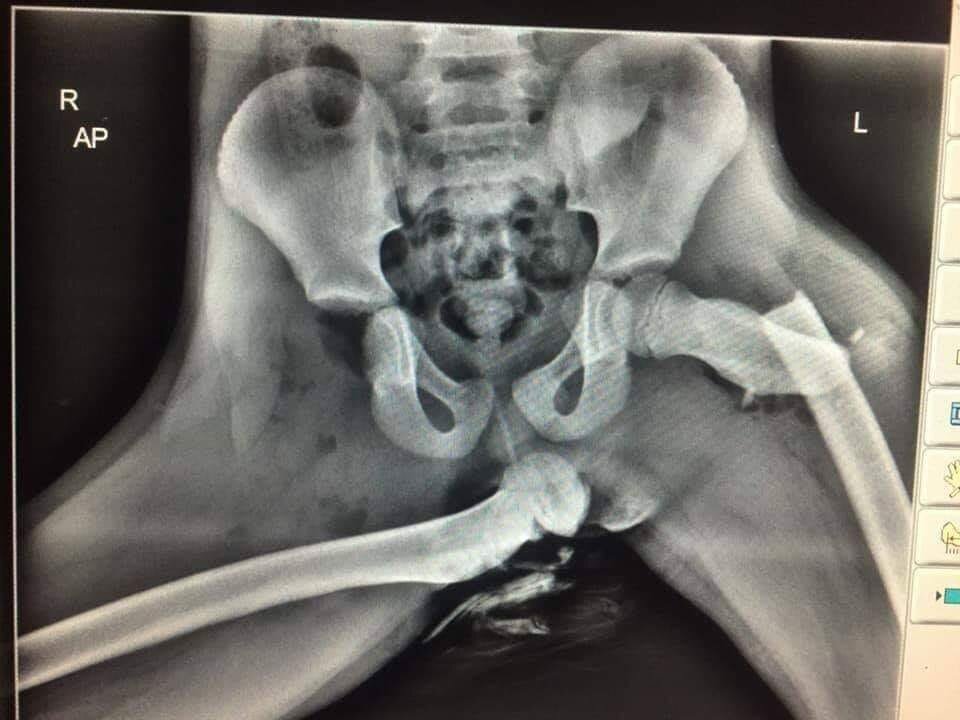

Почему не стоит класть ноги на приборную панель во время движения!!!

Девушка направлялась домой со свои мужем. Но в один момент мужчина не заметил впереди остановившуюся машину и резко затормозил, в этот момент ноги девушки находились на приборной панели, что спровоцировало перелом тазовой кости. В дальнейшем девушка проходила долгую реабилитацию. Также ей пришлось завязать со спортом .